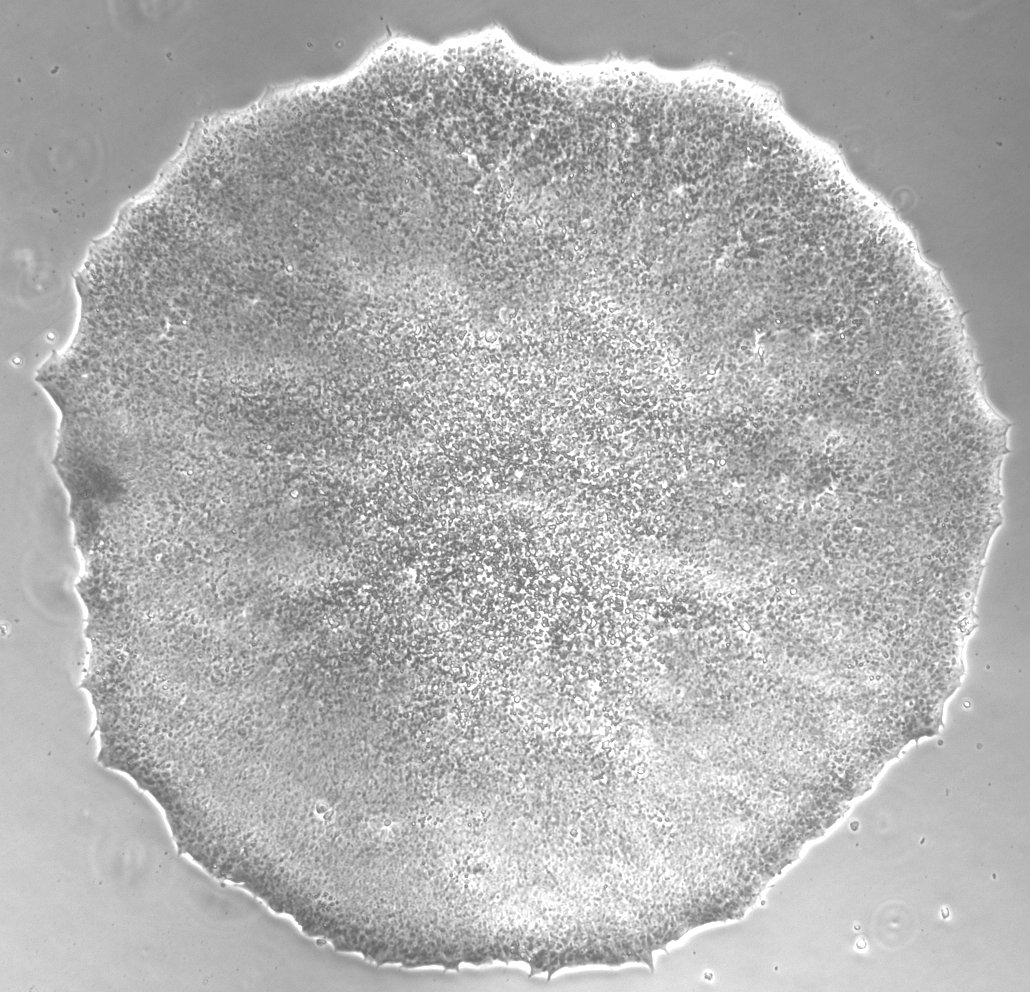

| Cell line type | Human induced pluripotent stem cell (hiPSC) |

| Selection criteria for clones | Morphology |

Analysis of Undifferentiated Cells

| Marker | Expressed | Immunostaining | RT-PCR | Flow Cytometry | Enzymatic Assay | Expression Profiles |

| NANOG |

Yes |

|||||

| SSEA-4 |